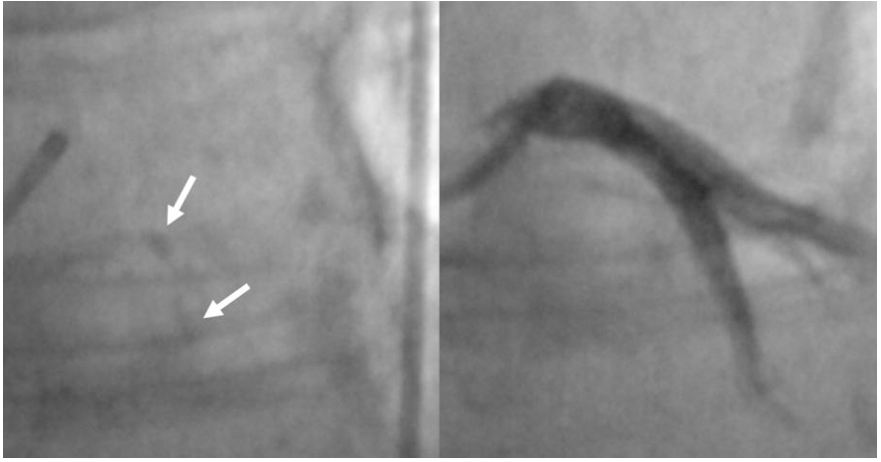

Coronary angiography (CA) has conventionally been used to assess and quantify CAC using fluoroscopy methods. In particular, a radiopacity detected only during the cardiac cycle before injection of the contrast dye, identifies a moderate calcification; a radiopacity detected without cardiac motion, visible on both sides of the arterial lumen, as a double track[21], identifies a severe or heavy calcification [Figure 2]. In this manuscript, the latter terms are similar. Fluoroscopy is very specific (98.7%) for detecting severe CAC, predicting worse stent expansion in these cases[22]. Still, its sensibility is low (40%-48%) compared to other intravascular imaging modalities, as demonstrated by a study conducted by Wang et al. CA often underestimates calcium, it is not able to measure calcium depth and its grading is inaccurate[23].

Figure 2. Severe calcification as “double track” radiopacity of Left Anterior Descending coronary artery, detected by coronary angiography (white arrow).

Nowadays, several technologically advanced tools such as add-on diagnostic CA are spreading; among these ones, the CoroFinder developed by Zaffino et al. deserves a special mention because of its ability to automatically identify coronary tree borders and to dynamically track the vessel position without contrast agents[24]. Also, the Dynamic Coronary Roadmap (DCM) (Philips, Amsterdam, Europe) is a commercial tool able to automatically generate a real-time, dynamic view of coronary arteries on fluoroscopy that can be used for navigation during PCI[25]. These innovative technologies could have a potential application in the field of CAC identification and quantification.